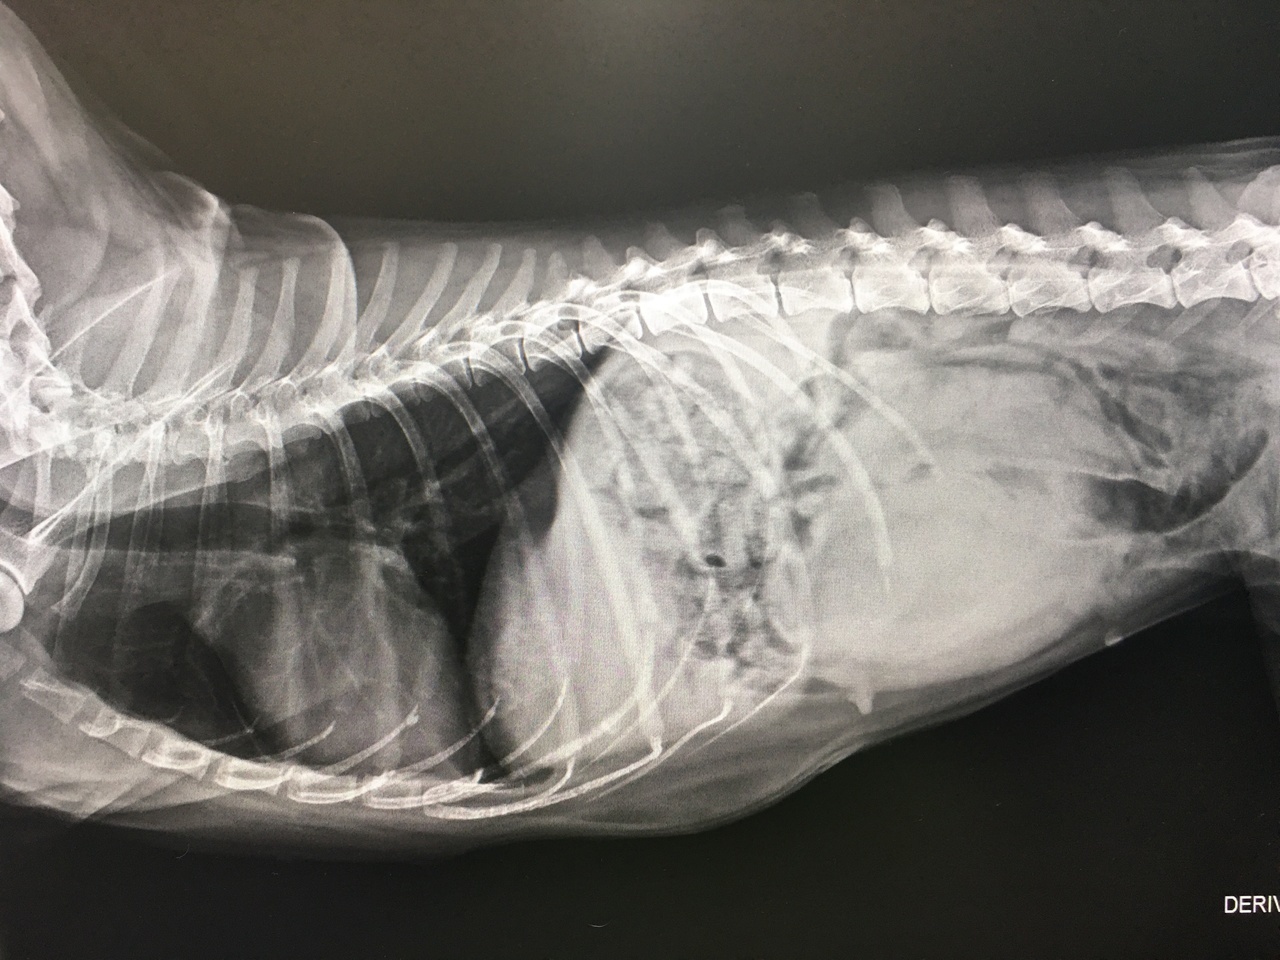

腹部に大きな腫瘤が認められる

卵巣腫瘍が見つかった柴犬、13歳齢

一日に何度もオエツがあるとのことでご来院され、レントゲン検査をしてみると、お腹の中に大きな腫瘤が見つかりました。

高齢だったので、麻酔に配慮しながら手術をし、お腹をあけて切除手術を行いました。